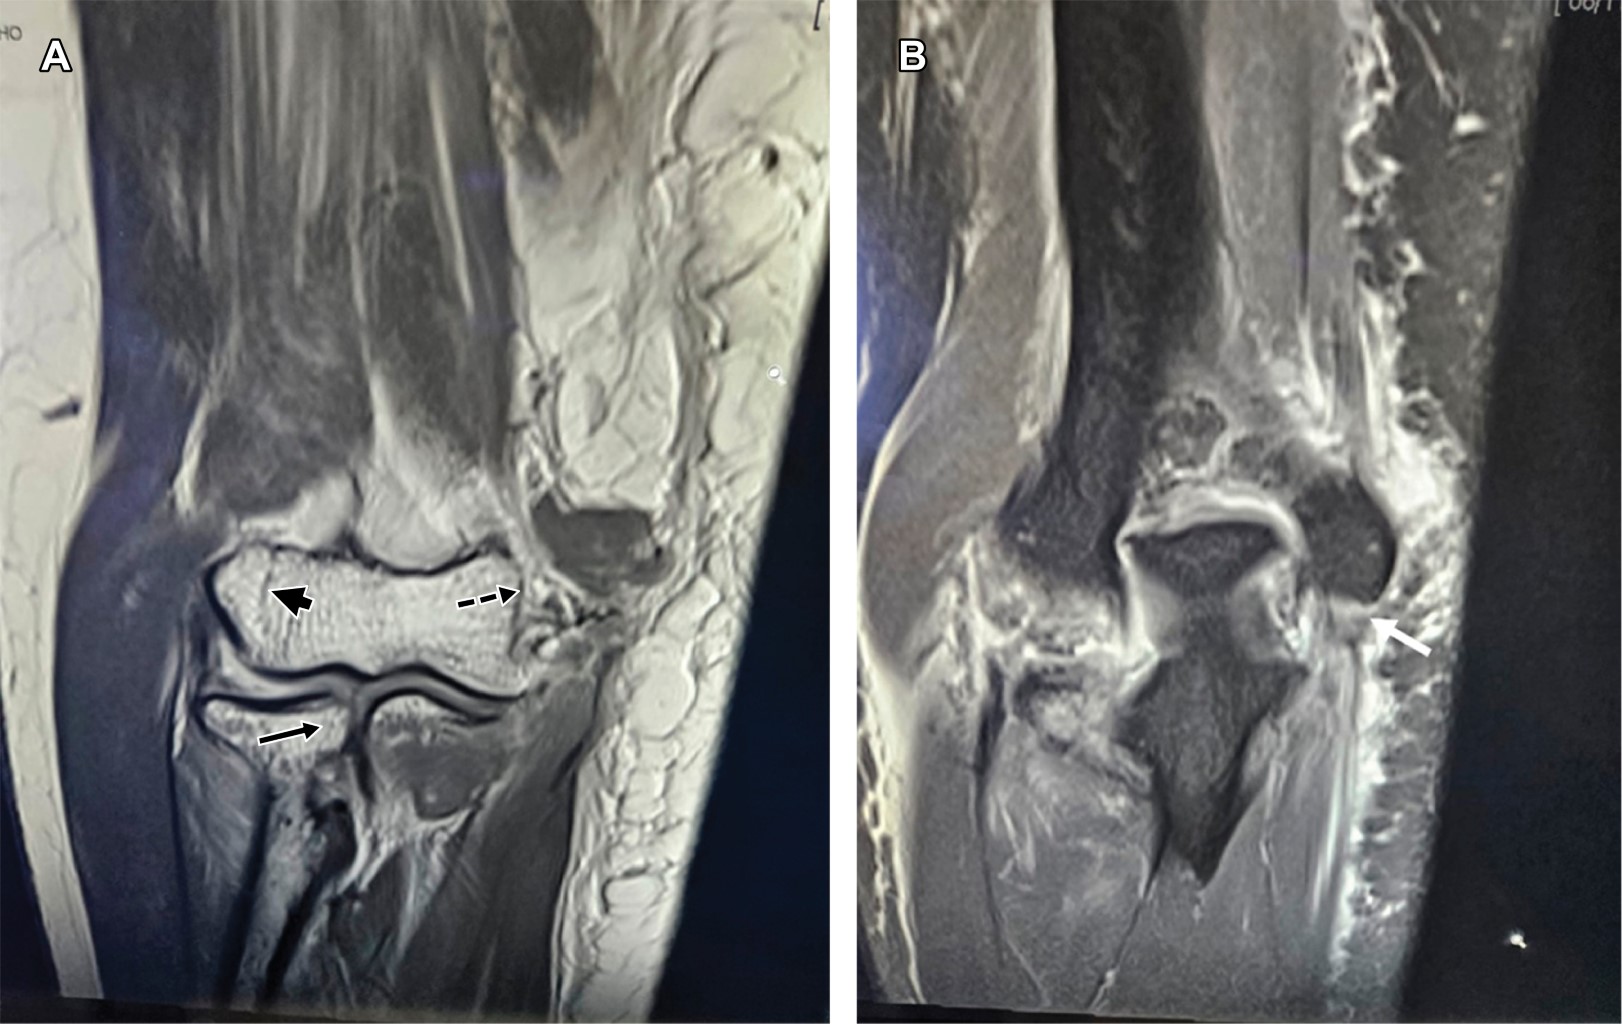

A la exploración dirigida se encuentra edema de codo, limitación para la flexión de los dedos, del carpo y ausencia de pronosupinación, sensibilidad conservada para nervios mediano y radial, hipoestesia en territorio del nervio cubital, con paresia 2/5 de músculos abductor, flexor corto y oponentes del quinto dedo. Con diagnóstico de probable fractura epitroclear se efectúa resonancia magnética (Figuras 1 y 2), la cual mostró: líneas de fracturas no desplazadas del capitellum humeral y de cabeza radial y edema óseo, fractura avulsión de epitróclea con desprendimiento de las inserciones del pronador redondo, palmar mayor, palmar menor, cubital anterior y flexor común superficial de los dedos, además de desprendimiento del ligamento anterior en su porción medial y del ligamento colateral medial del codo, incluyendo su fascículo posterior (ligamento de Bardinet), así como de la inserción medial del ancóneo, ruptura parcial del braquial anterior, hematoma en cara antero medial con extensión al compartimiento braquial posterior.

Figura 2